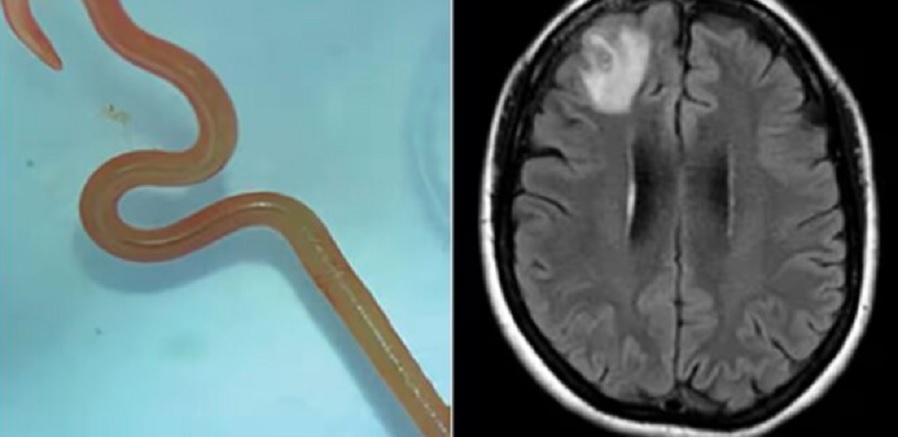

Фото: Canberra HealthНауковці вперше у світі повідомили, що знайшли в мозку австралійської жінки живого хробака завдовжки 8 сантиметрів.

Пізніше сканування виявило «атипову поразку в правій лобовій частині мозку». У червні 2022 році жінці провели операцію у столиці Австралії Канберрі та дістали з лобової частки червʼяка.

«Усі [в] операційній зазнали шоку всього свого життя, коли (хірург- ред.) взяв щипці, щоб виявити аномалію, а аномалія виявилася живим 8-сантиметровим світло-червоним червʼяком, що звивався. Навіть якщо прибрати фактор противності, це нова інфекція, яку ніколи раніше не реєстрували у людини», — сказав Санджая Сенанаяке, інфекціоніст лікар-терапевт з лікарні Канберри.